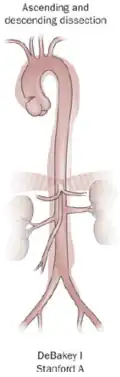

Several different classification systems have been used to describe aortic dissections. One such classification is based on chronicity and labels aortic dissections as hyperacute (<24 hours duration), acute (2–7 days), subacute (8–30 days), and chronic (>30 days).[20] The systems commonly in use are based on either the anatomy of the dissection or the duration of onset of symptoms before the presentation. The Stanford system is used more commonly now, as it is more attuned to the management of the patient.[38]

DeBakey

The DeBakey system, named after cardiothoracic surgeon Michael E. DeBakey, is an anatomical description of the aortic dissection. It categorizes the dissection based on where the original intimal tear is located and the extent of the dissection (localized to either the ascending aorta or descending aorta or involving both the ascending and descending aorta).[39]

- Type I – originates in ascending aorta, and propagates at least to the aortic arch and often beyond it distally. It is most often seen in patients less than 65 years of age and is the most lethal form of the disease.

- Type II – originates in the ascending aorta and is confined to it.

- Type III – originates in the descending aorta and rarely extends proximally, but will extend distally. It most often occurs in elderly patients with atherosclerosis and hypertension.

Stanford

The Stanford classification is divided into two groups, A and B, depending on whether the ascending aorta is involved.[40]

- A – TAAD involves the ascending aorta and/or aortic arch, and possibly the descending aorta. The tear can originate in the ascending aorta, the aortic arch, or more rarely, in the descending aorta. It includes DeBakey types I and II.

- B – TBAD involves the descending aorta or the arch (distal to the left subclavian artery), without the involvement of the ascending aorta. It includes DeBakey type III.

The Stanford classification is useful as it follows clinical practice, as type A ascending aortic dissections generally require primary surgical treatment, whereas type B dissections generally are treated medically as initial treatment with surgery reserved for any complications.[41]